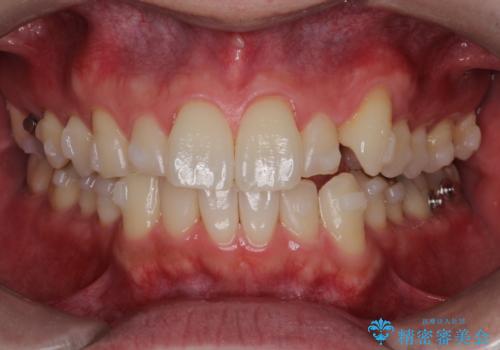

- 前歯の凸凹と顎の偏位を主訴に来院されました。

下顎の偏位を認めましたが、外科矯正を希望されなかったためできる範囲で顎の偏位を治すことができるよう治療を行なっております。

治療開始前に、下顎位の評価をおこなうことで、完成度の高い治療を行うことができました。